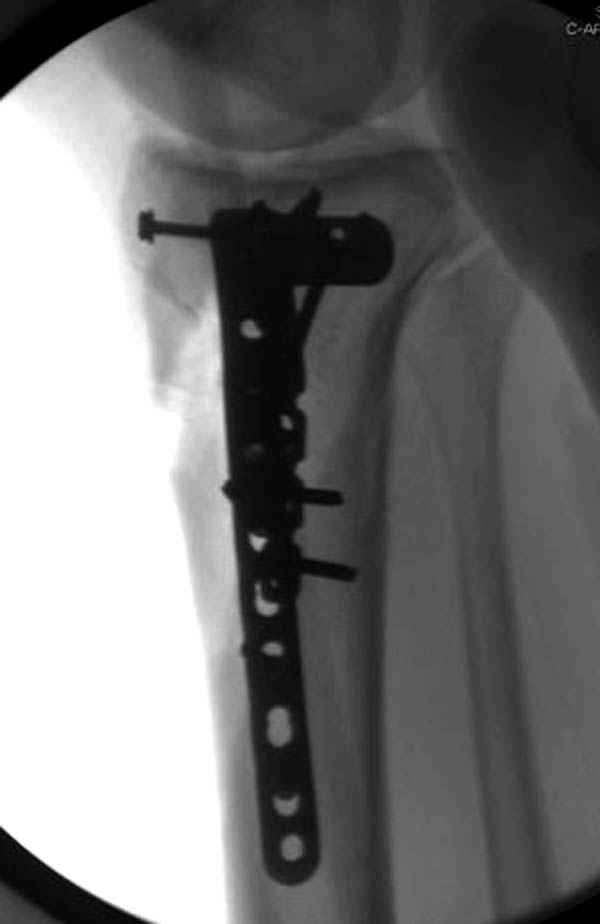

Трудно поверить, что разрекламированная Ортопедическая школа Восточной Украины позволяет такие странные снимки? На прямом снимке сохранен общий контур плато, но не известна судьба импрессии суставной поверхности. На полубоковой?, оставлен без репозиции задне-медиальный отдел, и навряд ли после такой фиксации можно удовлетвориться результатом.

Такая ситуация характерна для многих, когда принимается ошибочное решение, т.е пытаются фиксировать одним имплантом переломы двух мыщелков. Латеральная пластина приемлема только для тех случаев, когда сохраняется интактным медиальный диафизарный кортекс и отсутствует фрагментация на верхушке медиального перелома.